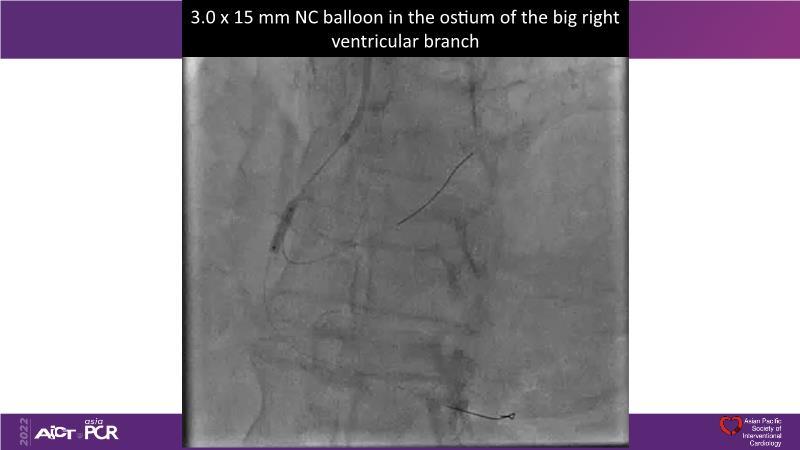

Consult this session to understand the technology and scientific evidence of the novel sirolimus drug-coated balloon, to learn its utility for PCI in a variety of lesion and patient subsets and to understand the evidence and outcomes in real-world patients.

- To understand the technology and scientific evidence of the novel sirolimus drug-coated balloon (SDCB)

- To learn the utility of the DCB for PCI in a variety of lesion and patient subsets